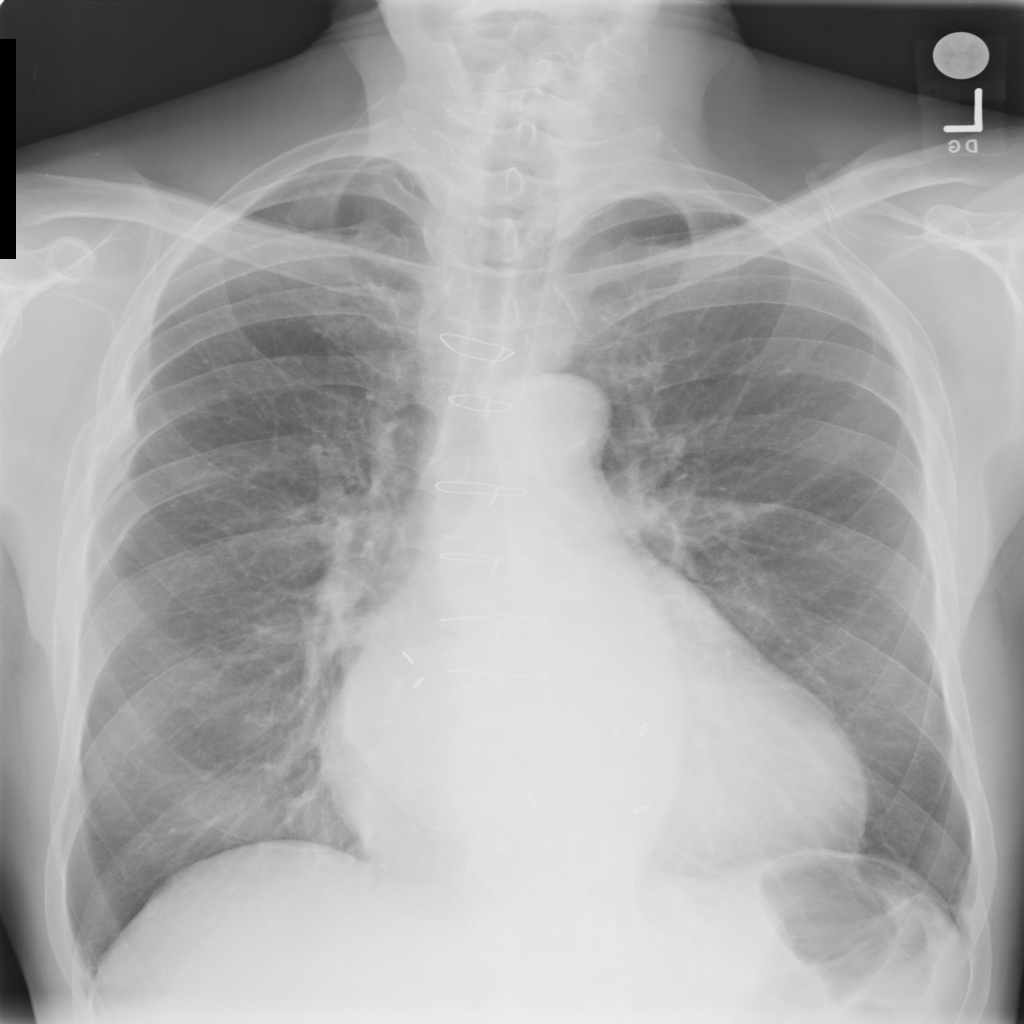

Showing up to 90 reference images for Cardiomegaly.

PAT-4639 · IMG-045Cardiomegaly

PAT-4639 · IMG-045

PA